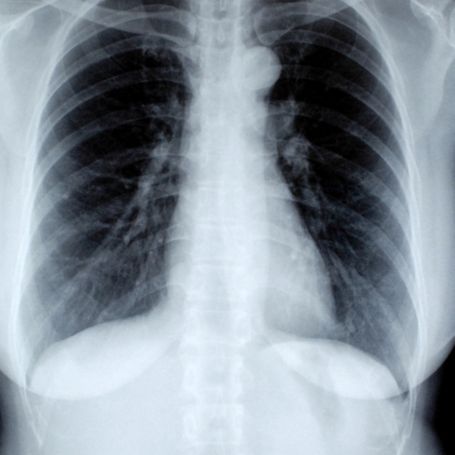

The ABDOMEN (STANDING) VIEW is a specialized X-ray imaging test designed to examine the organs and structures within the abdominal cavity. It helps doctors detect abnormal gas patterns, fluid levels, perforations, or blockages within the digestive tract. This imaging view is typically taken while the patient is standing upright, allowing the radiologist to assess the effect of gravity on abdominal organs, and to identify the presence of free air or fluid that may not be visible in a lying (supine) position.

The patient is asked to stand upright in front of the X-ray machine. The radiology technician adjusts the equipment to focus on the abdominal region and instructs the patient to remain still while the X-ray is taken. In some cases, additional supine or lateral views may be taken for better clarity. The procedure is simple, takes only a few minutes, and requires no special preparation unless specified by your doctor.

The parameters evaluated during an ABDOMEN (STANDING) VIEW** include:

1. Gas distribution in the stomach, intestines, or colon.

2. Air-fluid levels suggesting bowel obstruction.

3. Detection of free intra-abdominal air indicating perforation.

4. Organ size, position, and abnormal calcifications.

The results are analyzed by specialists at Diagnopein to identify possible medical issues such as intestinal blockage, perforated ulcers, or complications related to abdominal surgeries. A detailed radiology report is then shared with the physician to assist with further management.